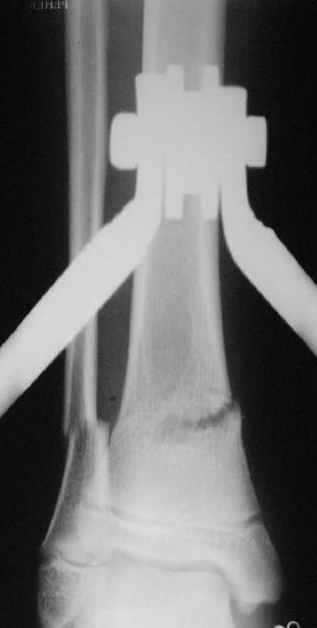

Промежуточный

Нашел в комп-ре схожий случай:

1) з/репозиция, 2) фиксация 2 спицами, 3) аппарат, 4) фиксационные

спицы удалены...

См. аттачт.

А можно было наложить аппарат и по поводу ложного сустава...

По крайней мере не было бы укорочения (пусть и в 2 см)...